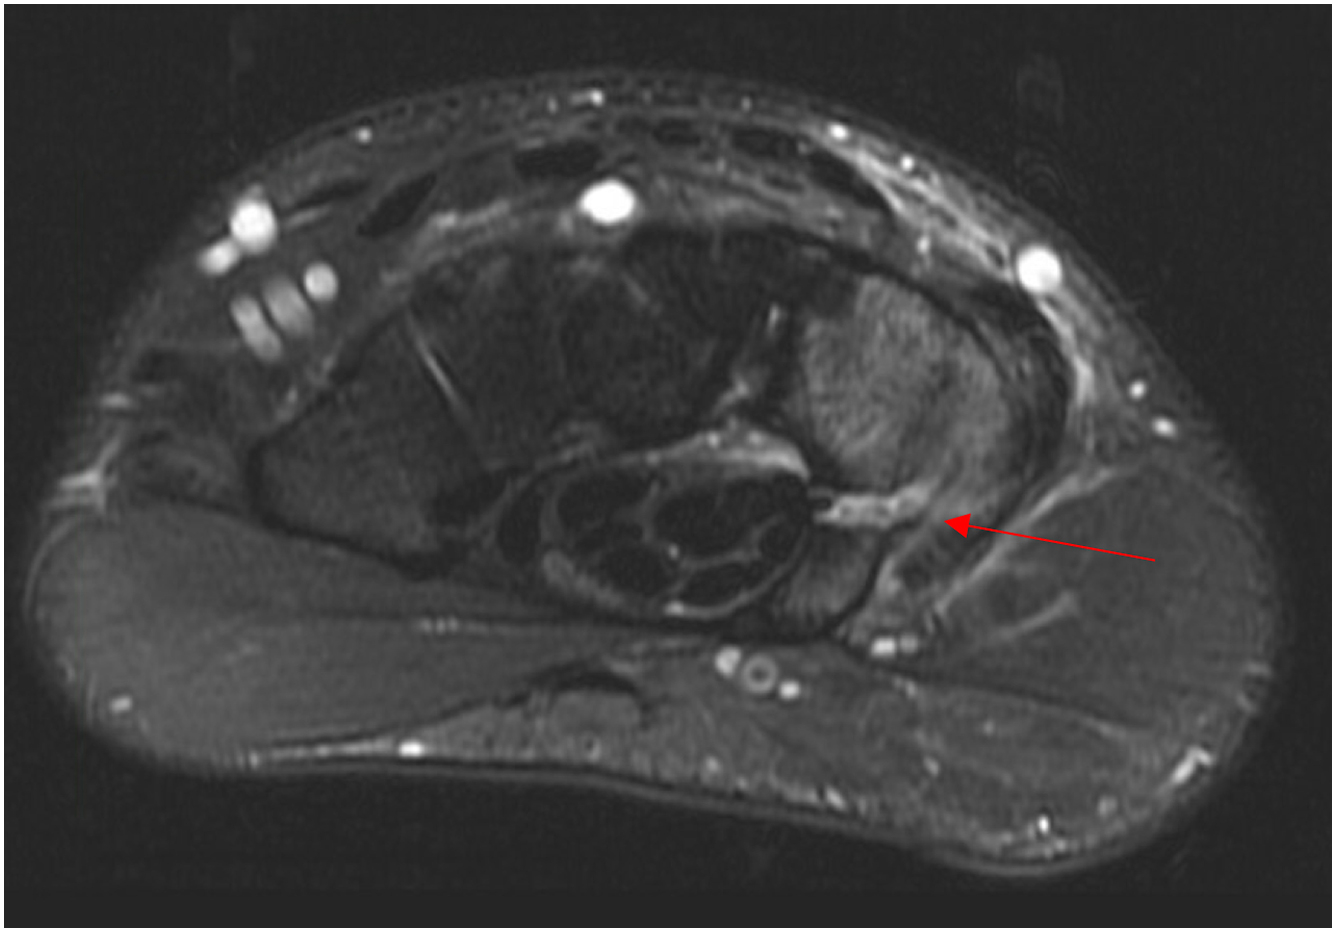

Dynamic evaluation of the ECU tendon may be performed using ultrasound. However, areas of tenosynovitis, tendinopathy, and position of the tendon within the ECU tendon groove may be evaluated on MRI ( Fig. 5 A ). MRI may also help differentiate ECU pathology from other diagnoses. Initial treatment of ECU pathologies may include rest, avoidance of aggravating activities, and immobilization. Immobilization may be performed for 4 to 6 weeks with the wrist in extension and radial deviation and the forearm in pronation to prevent tendon subluxation. Healing can be monitored periodically with MRI or ultrasound. For patients with recalcitrant pain or instability, surgical intervention can be considered. Surgical procedures range from tendon debridement, ECU subsheath repair, to ECU subsheath reconstruction ( Figs. 5 B; 6 ). Postoperatively, patients may undergo a short period of immobilization for tendon debridement procedures, or for a longer period (ie, 4–6 weeks) in extension, radial deviation, and pronation for cases of instability. Athletes may then initiate therapy for range of motion and strengthening, with return to play considered no earlier than 3 to 4 months postoperatively.